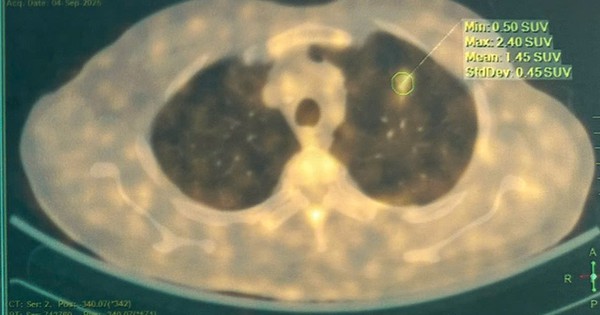

Trí tuệ nhân tạo (AI) phân tích hình ảnh chẩn đoán (CT scan) giúp phát hiện sớm các nốt tổn thương phổi, tăng độ chính xác và tối ưu hóa thời gian chẩn đoán ung thư.